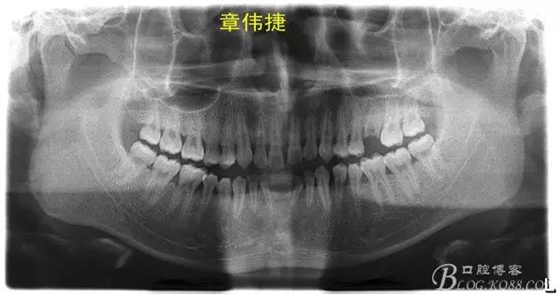

術(shù)前資料: